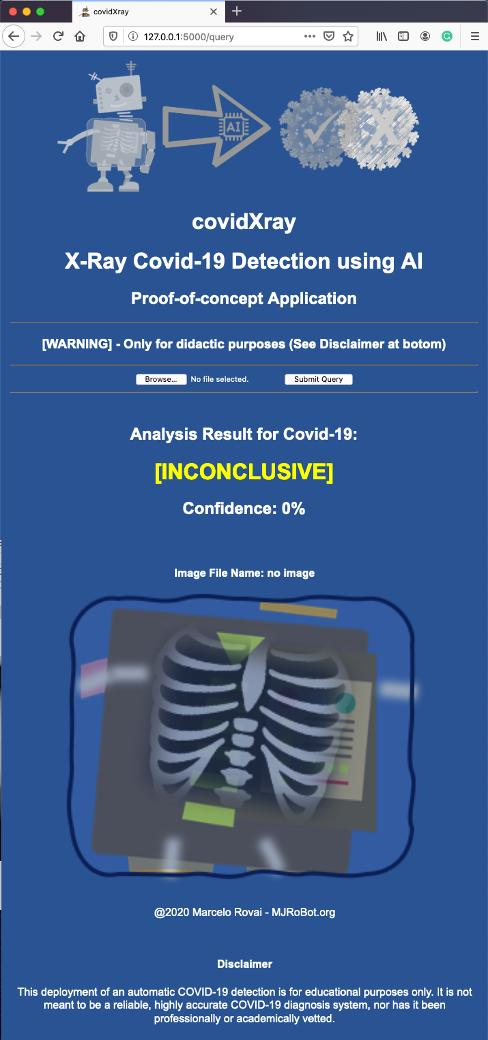

下图为我们提供了最终应用程序如何工作的基本概念:

X光扫描胸部图像(User_A.png),应用程序将图像存储在web应用程序的计算机上,决定图像是否属于受病毒污染的人(模型预测:[阳性]或[阴性])。在这两种情况下,应用程序都会输出预测的准确性(模型准确度:X%)。

为了避免两者都出错,将向用户显示原始文件的名称及其图像。图像的新副本存储在本地,其名称添加一个预测标签,并且加上准确度。

应用程序将在你的本地网络中运行: